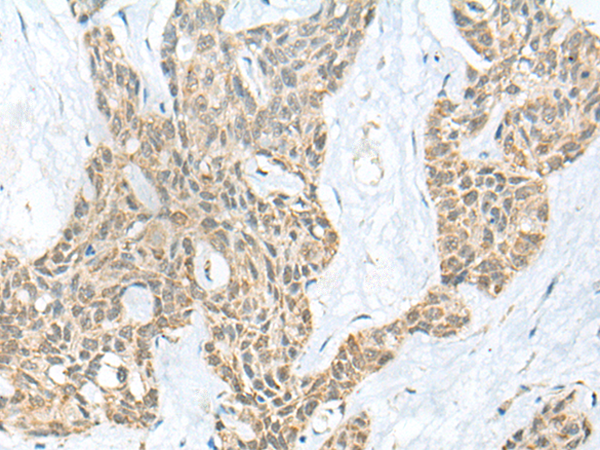

IHC positive control: |

Human esophagus cancer |